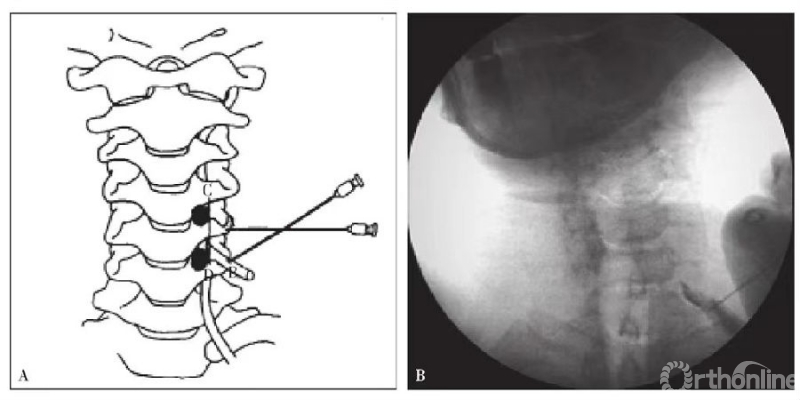

(1)6号或者9号腰椎穿刺针,透视下穿刺至神经根出口区(图1):

图1 穿刺示意图 A.冠状位中线旁开约4cm,平横突下沿进针,向内偏20°;B.矢状位上平横突下沿进针,向下偏约20°(图片引用自:Tajima T, Furukawa K,Kuramochi E.Selective lumbosacral radiculography and block.Spine,1980,5(1):68-77)

1)正位影像:相应椎体椎弓根下缘中点,下位椎体上关节上缘;

2)侧位影像:侧位椎间孔后缘1/3;

3)S1在第一骶神经孔;

4)准确穿刺到神经根,会诱发出神经根相应支配区域的放射痛,并术中询问患者是否能够复制术前下肢症状;